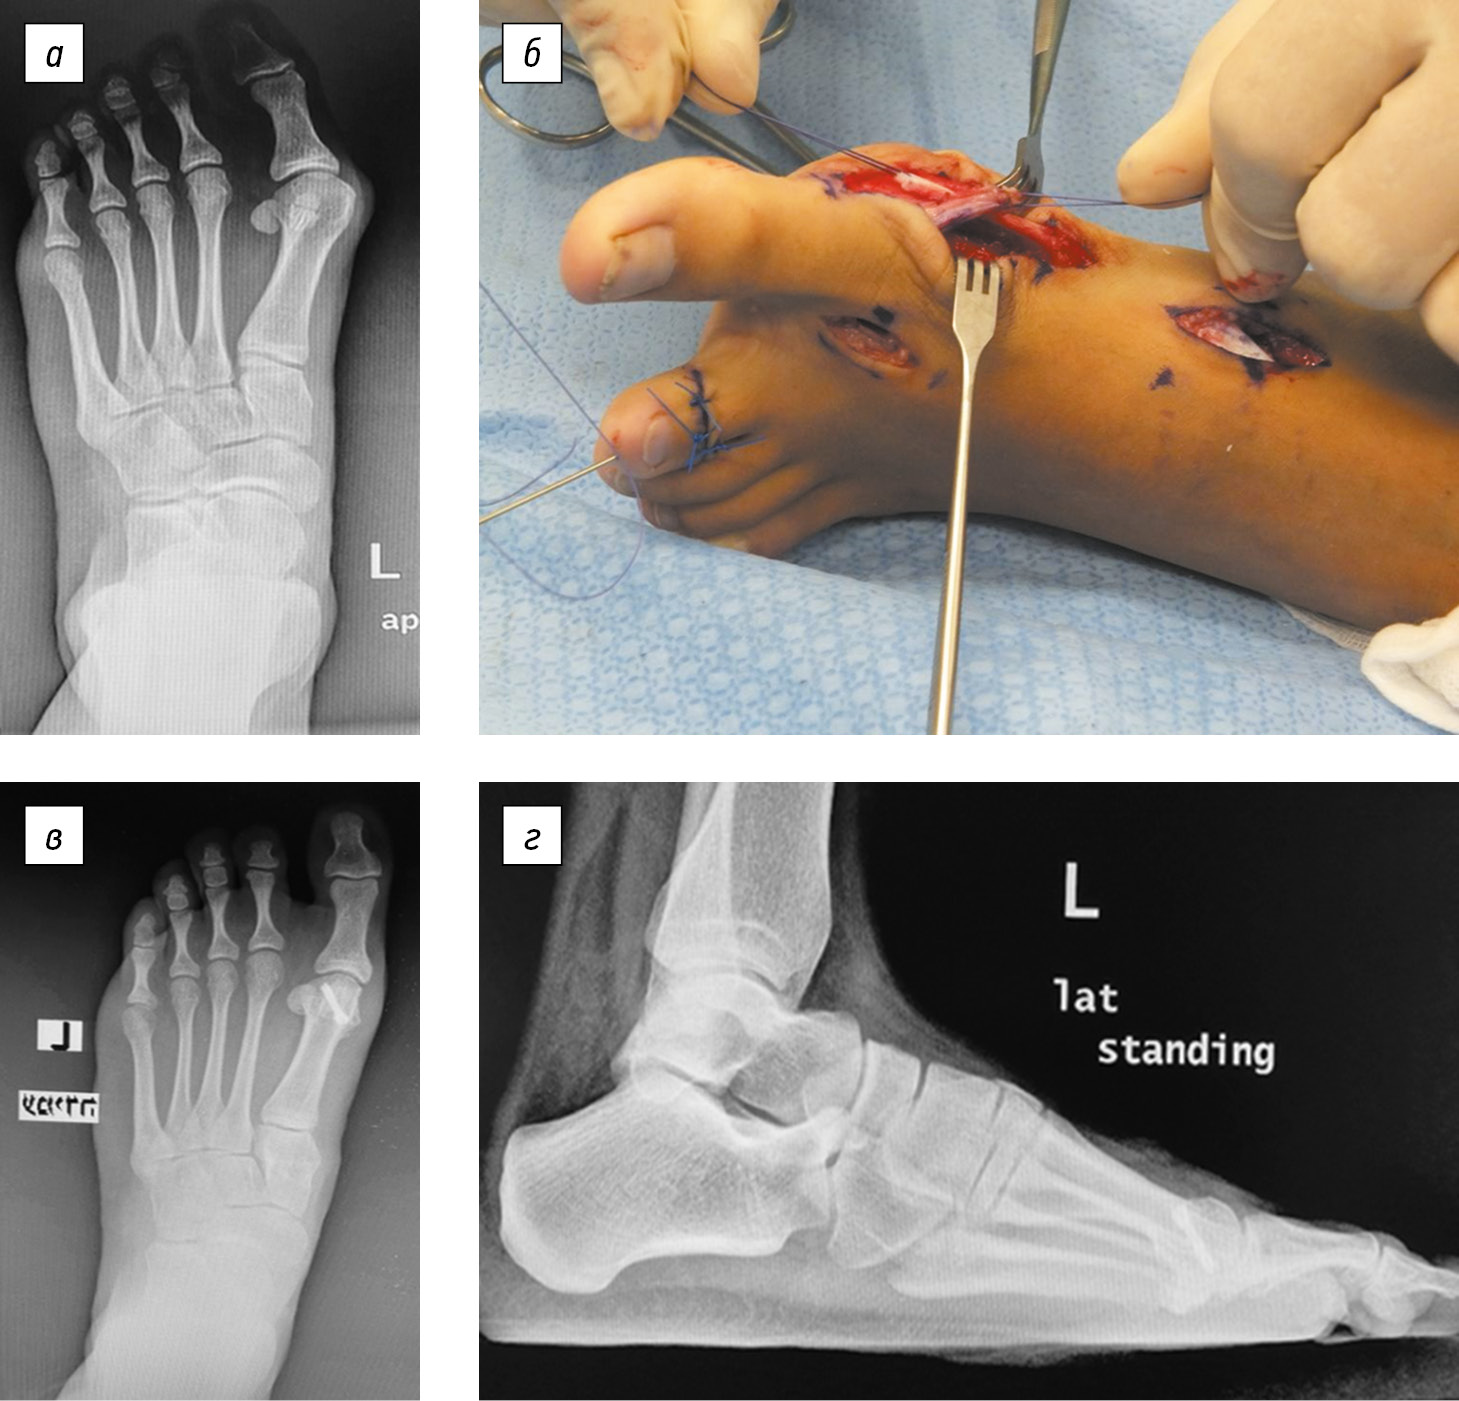

Clinical case

A 13-year-old female patient complained of pain in the anteromedial parts of the feet, mostly on the left, which aggravated when wearing shoes. Examination revealed hallux valgus with varus deviation of the first metatarsal bone and hyperemia in the region of the medially protruding head of the first metatarsal bone. There was also a pronounced hammer-shaped deformity of the second toe of the left foot. The patient was unable to retract actively her big toes (toe spread test). A radiograph of the left foot under load revealed a hallux valgus deformity of the big toe of the left foot (Fig. 6, a). Corrective osteotomy with restoration of muscle balance (Fig. 6, b) according to our method was performed under anesthesia on September 13, 2016. The deformity of the second toe was corrected. The postoperative period was uneventful. After 6 weeks, the plaster cast was removed; after additional 2 weeks of walking in a special hard sandal, full load was allowed. Movements in the first metatarsophalangeal joint and active abduction of the big toe were fully restored. The patient has no complaints, and she returned to active sports. Two years after surgery on the left foot, the operation on the right foot was successful. Figure 6, c, d presents frontal and lateral radiographs of her left foot under load 36 months after the surgery.

Fig. 6. Patient, 13 years old. Hallux valgus deformity of the big toe of the left foot: a, X-ray image in frontal projection before surgery; b, stage of surgery with the transfer of the dorsal–distal part of the tendon of the musculus abductor hallucis, and it was sutured with tension to the base of the triangular medial capsular flap; c, frontal X-ray image 36 months after the surgery showing correction of the deformity and complete consolidation of osteotomies; d, lateral X-ray image